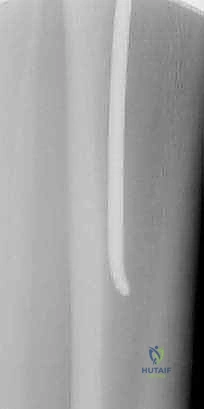

- المسامير النخاعية المرنة (Flexible Intramedullary Nails - TENs): وهي تقنية حديثة ومثالية للأطفال. يتم إدخال مسامير مرنة من التيتانيوم داخل تجويف العظم عبر شقوق صغيرة جداً (Minimally Invasive). تعمل هذه المسامير كدعامة داخلية تسمح للعظم بالالتئام بسرعة دون فتح جراحي كبير، وتوفر ثباتاً ممتازاً.